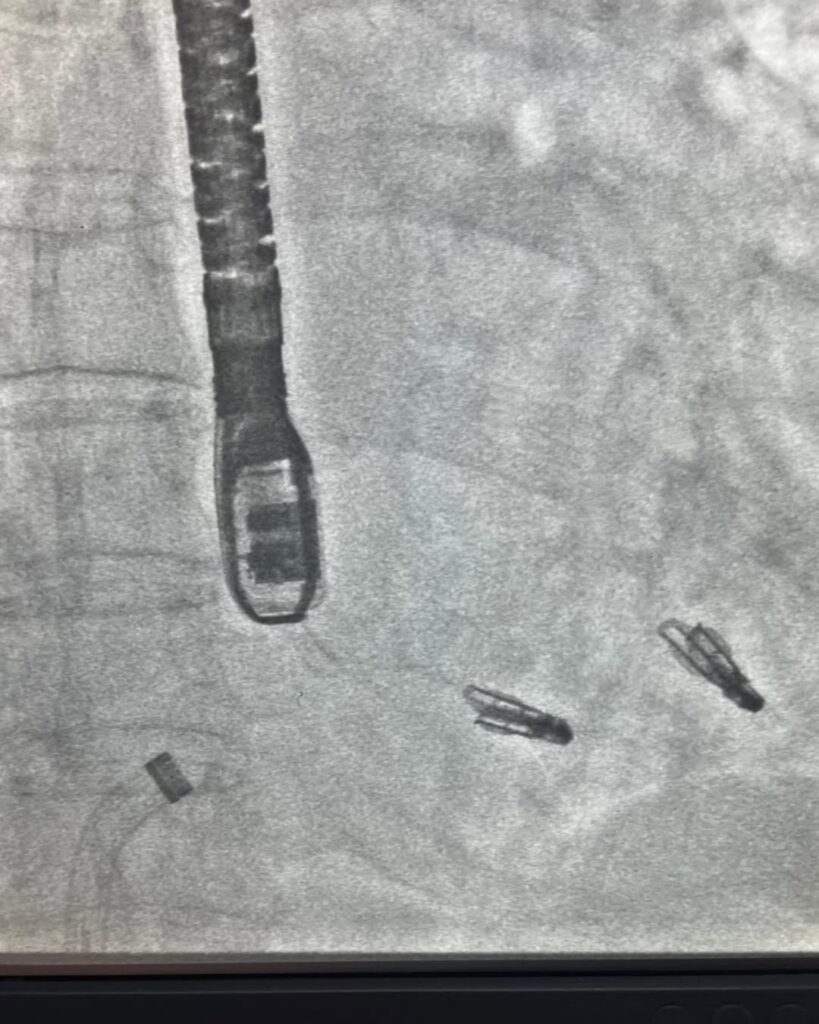

Özellikle aort kapak darlıklarında, anjiyo yöntemi ile kapak değişimi olarak bilinen TAVI uygulaması uzun süredir Ada Hastanesi’nde başarıyla uygulanıyor. Ayrıca mitral kapak yetmezliklerinde MitraClip, triküspid kapak yetmezliklerinde ise Triclip yöntemi etkili bir tedavi seçeneği olarak tercih ediliyor.

Ada Hastanesi, bölgede bir ilke imza atarak aynı seansta hem MitraClip hem Triclip uygulamasını iki hastada başarıyla gerçekleştirdi. Minimal invaziv yöntemlerin en büyük avantajı, kasık toplardamarından girilerek yapılması sayesinde hastada herhangi bir kesik veya cerrahi iz bırakmaması. Bu sayede hastalar yalnızca 1-2 gün içinde taburcu edilip kısa sürede normal yaşamlarına dönebiliyor.